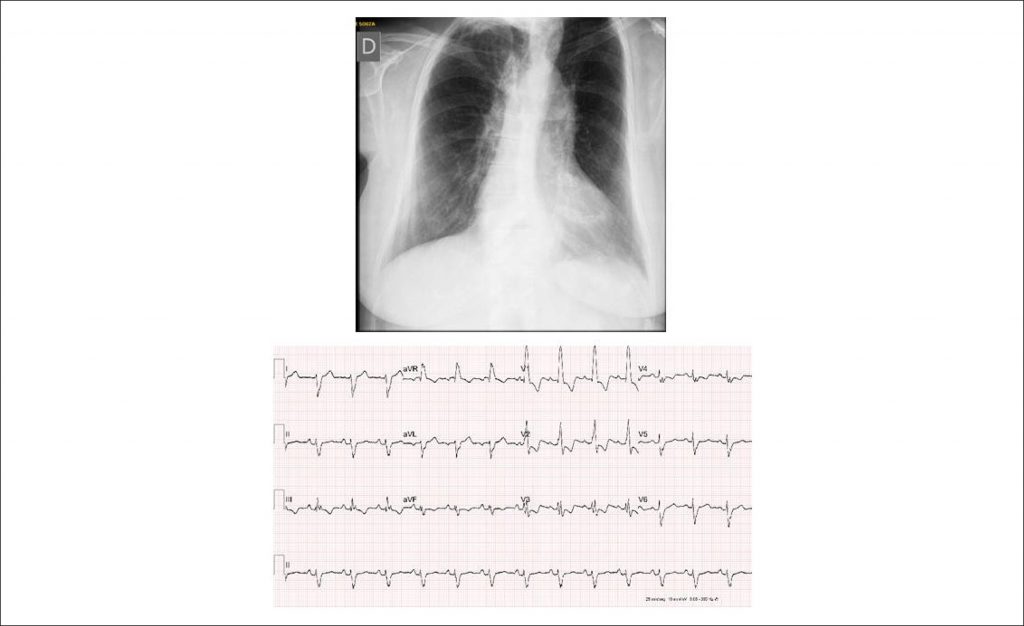

Case 5/2018 – Severe Pulmonary Valve Stenosis (PVS), Relieved by a Double-balloon Catheter, in a 68-year-old Woman

During a recent clinical evaluation for cholecystectomy surgery, a heart murmur was auscultated and complaint of fatigue at great efforts lasting for some months was reported by the patient. The diagnosis of severe PVS was attained, with a maximum gradient of 160 mmHg obtained at the echocardiography. The patient denied other symptoms and was unaware of the existence of this cardiopathy. She had no history of other morbidities and took vitamin D.

Physical examination: The patient was in good overall condition, eupneic, acyanotic, normal pulses in the 4 limbs. Weight: 70 kg, height: 160 cm, right upper limb blood pressure: 140/80 mmHg, heart rate: 80 bpm, oxygen saturation, 89%. Aorta not palpable in the suprasternal notch.